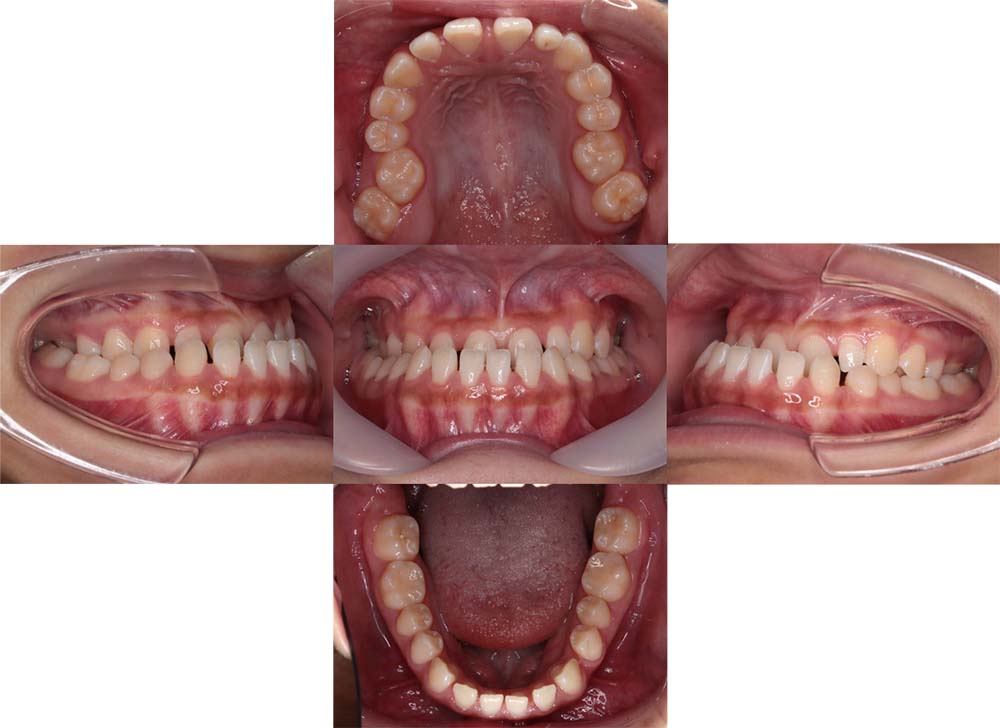

症例02

| 主訴 | 下あご顎が出ている。曲がっている。 |

| 診断名あるいは主な症状 | 反対咬合、非対称、空隙歯列、過蓋咬合 |

| 年齢/性別 | 19歳・女性 |

| 矯正ステージ | 大人の矯正治療 |

| 治療方法 | ワイヤー矯正、顎矯正手術の施行 |

| 抜歯部位/抜歯有無 | 非抜歯 |

| 治療内容 | 上下顎歯列を並べた後に顎矯正手術の施行。 |

| 費用 | 保険治療 |

| 治療期間 | 3年2ヶ月 |

| 主なリスク・副作用 | 痛み、歯根吸収、歯肉退縮、虫歯、後戻り |